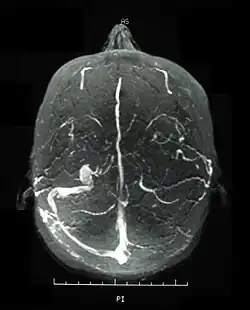

Inflammatory eye disease can develop early in the disease course and lead to permanent vision loss in 20 percent of cases. Ocular involvement can be in the form of posterior uveitis, anterior uveitis, or retinal vasculitis. Anterior uveitis presents with painful eyes, conjuctival redness, hypopyon, and decreased visual acuity, while posterior uveitis presents with painless decreased visual acuity and visual field floaters. A rare form of ocular (eye) involvement in this syndrome is retinal vasculitis which presents with painless decrease of vision with the possibility of floaters or visual field defects.[4]

Visual acuity, or color vision loss with concurrent mucocutaneous lesions or systemic Behçet's disease symptoms should raise suspicion of optic nerve involvement in Behçet's disease and prompt a work-up for Behçet's disease if not previously diagnosed in addition to an ocular work-up. Diagnosis of Behçet's disease is based on clinical findings including oral and genital ulcers, skin lesions such as erythema nodosum, acne, or folliculitis, ocular inflammatory findings and a pathergy reaction. Inflammatory markers such ESR, and CRP may be elevated. A complete ophthalmic examination may include a slit lamp examination, optical coherence tomography to detect nerve loss, visual field examinations, fundoscopic examination to assess optic disc atrophy and retinal disease, fundoscopic angiography, and visual evoked potentials, which may demonstrate increased latency. Optic nerve enhancement may be identified on Magnetic Resonance Imaging (MRI) in some patients with acute optic neuropathy. However, a normal study does not rule out optic neuropathy. Cerebrospinal fluid (CSF) analysis may demonstrate elevated protein level with or without pleocytosis. Imaging including angiography may be indicated to identify dural venous sinus thrombosis as a cause of intracranial hypertension and optic atrophy.